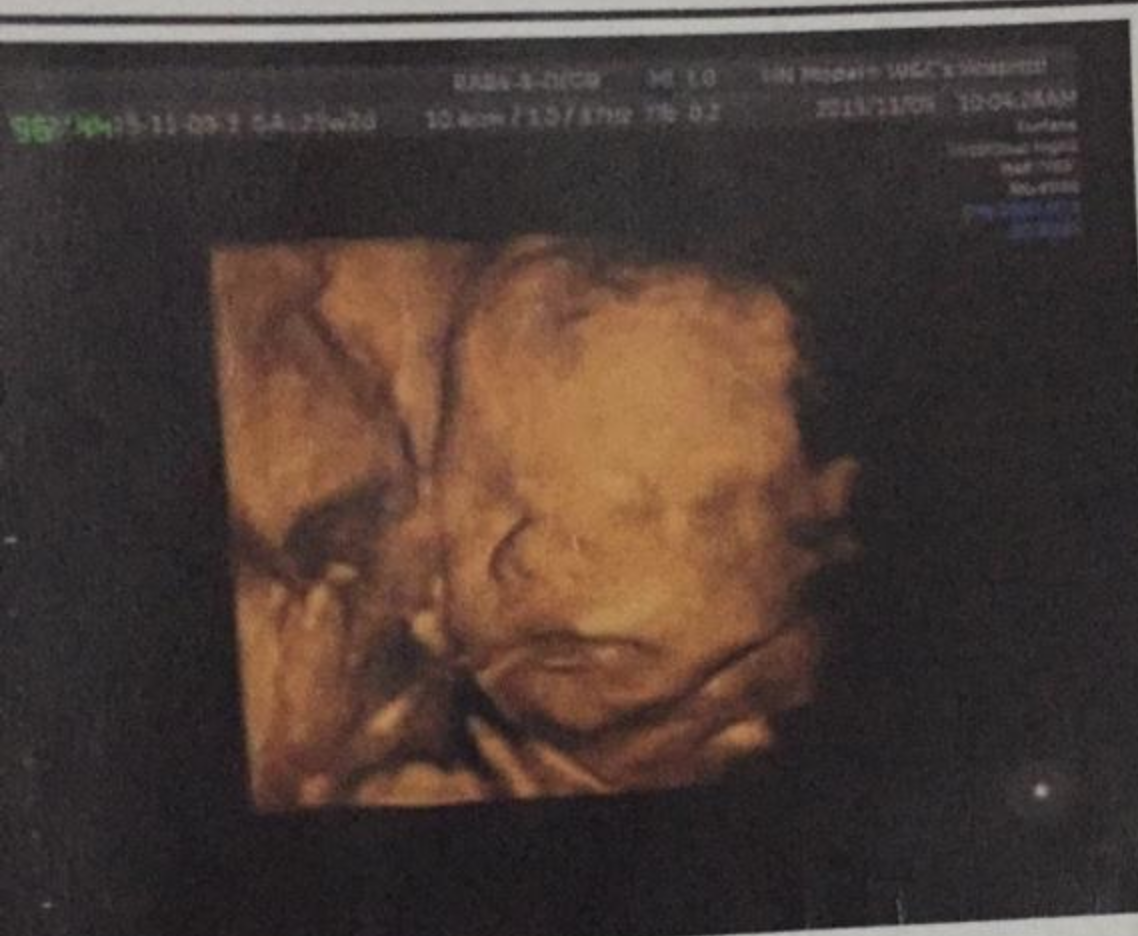

有妈妈说怀孕26周去做B超,发现胎儿右侧鼻骨缺失,后来做了羊水穿刺,结果正常,他们一咬牙决定保留这个孩子,后来孩子出生了,有鼻子,很健康,下面这是那个宝宝。